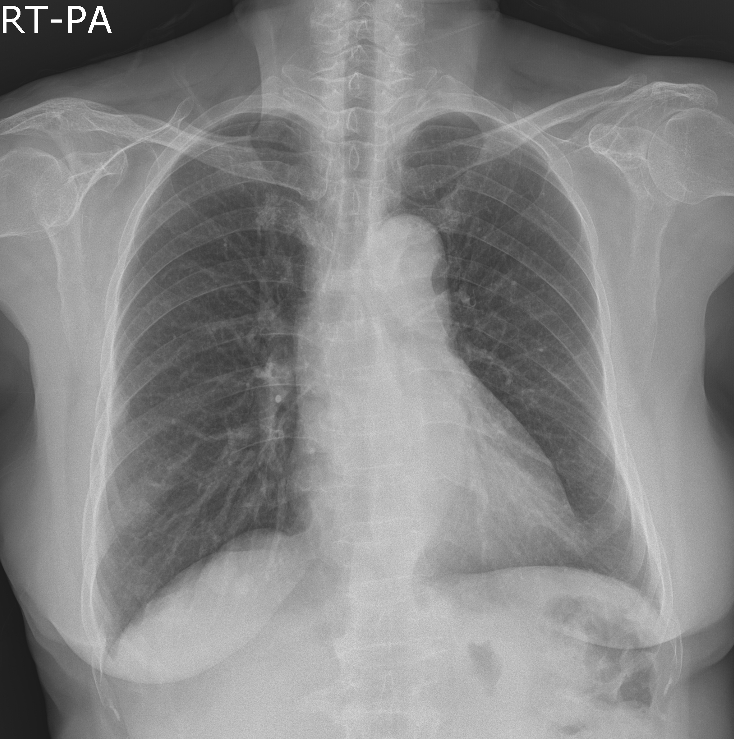

63¼¼ ¿©È¯

°©»ó¼±¾ÏÀ¸·Î ¼ö¼ú ¿¹Á¤À¸·Î, ¼ö¼ú Àü evaluation »ó¿¡¼­ CXR abnormality ÀÖ¾î

chest CT ±îÁö ½ÃÇàÇÏ¿´½À´Ï´Ù.